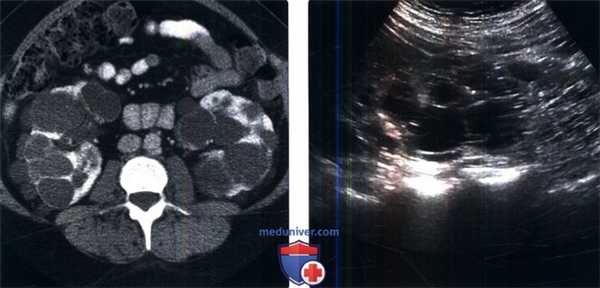

(Слева) Т2-ВИ, режим подавления сигнала от жировой ткани, аксиальная проекция: у пациента с аутосомно-доминантной поликистозной болезнью почек и поликистозной болезнью печени выявлены множественные кисты левой почки и печени.

(Справа) УЗИ печени, поперечная плоскость сканирования: у того же пациента выявлены множественные простые анэхогенные кисты печени. Поликистозную болезнь печени часто выявляют у пациентов с аутосомно-доминантной поликистозной болезнью почек. Печень обычно увеличена. Кисты печени бывают внутрипеченочными и перибилиарными.д) Клинические особенности: